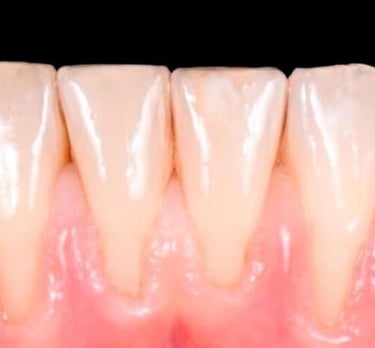

ORTODONCIA

La ortodoncia corrige dientes mal posicionados y mejora la oclusión, favoreciendo tanto la estética como la salud bucal.

En IdenClinic tratamos a niños y adultos con distintos sistemas: brackets metálicos, estéticos y ortodoncia invisible.

Esta última utiliza férulas transparentes que pasan inadvertidas y alinean los dientes de forma progresiva y cómoda.

Analizamos cada caso con precisión digital y planificaciones personalizadas, logrando una sonrisa armónica, una mordida funcional y resultados estables sin comprometer la imagen del paciente durante el tratamiento.